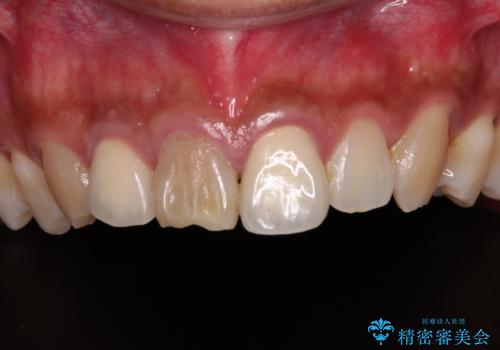

- 前歯の変色した歯を治したいことを主訴として来院された患者様です。

数年前、外傷により両隣の歯とともに根管治療を行い、その後両隣の歯はオールセラミッククラウンにて補綴したそうです。

時間の経過とともに、セラミックにしなかった当該歯の変色が目立つようになり、オールセラミッククラウンにて補綴することとしました。